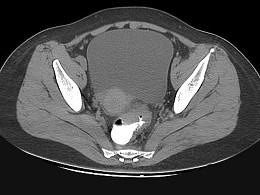

问题 男,67岁,排便习惯改变,血便三个月入院,CT检查如图所示,下列说法错误的是 ( )

选项 A、此为直肠息肉 B、此为直肠癌 C、其表面欠光整,边界欠清晰 D、可做直肠指检及活检以确定病变性质 E、直肠肠腔局限性增厚

答案 A